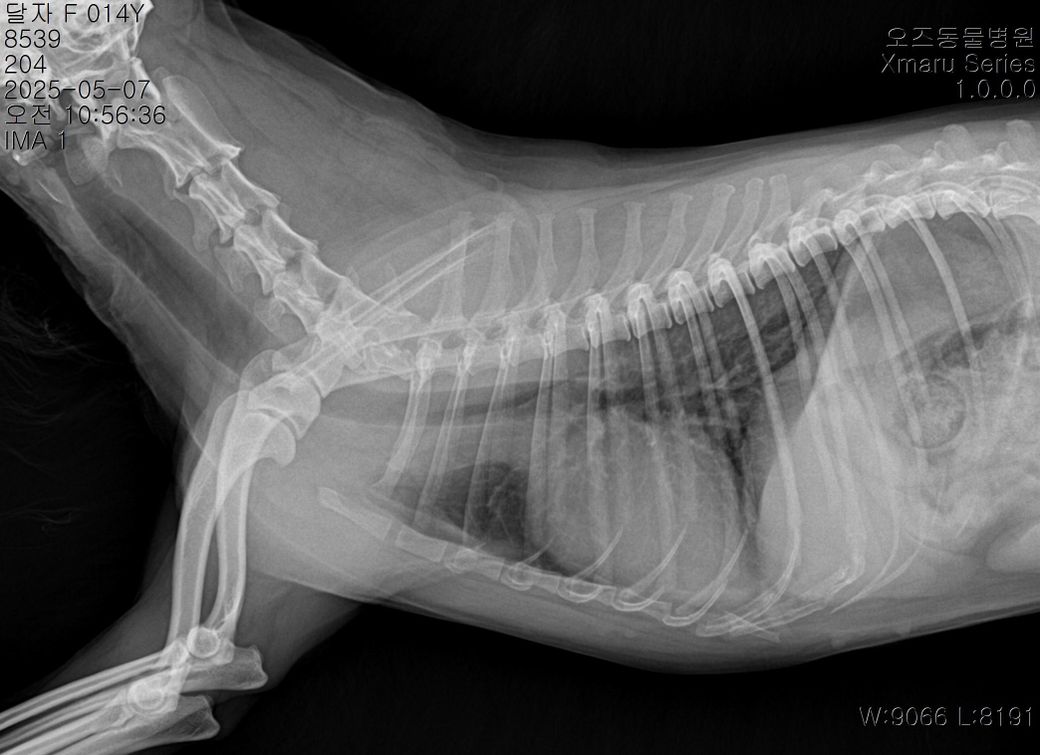

그리고 이번에 찍은 엑스레이 사진 판독으로 현재 어떤지 봐주시겠어요

아래사진이 현재구요

현재사진은 세번째 다른병원에서 찍은 사진입니다